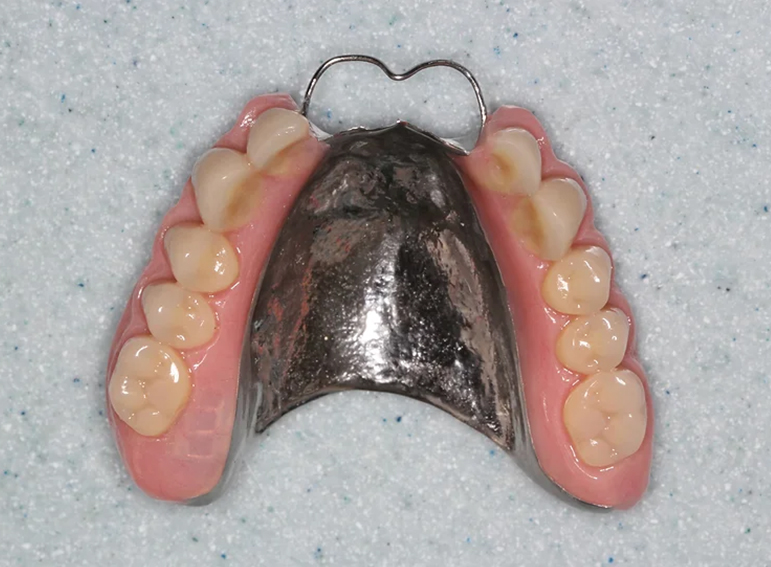

Upper and lower dentures (with implants) after broken jaws.